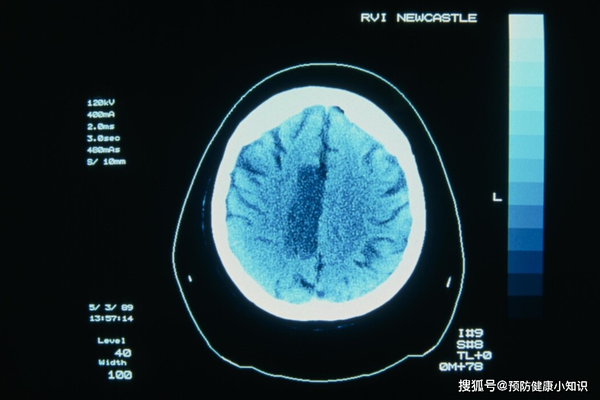

經過醫生檢查,王剛確診為突發性腦梗,雖然全力搶救,但是並沒有挽回王剛的生命。